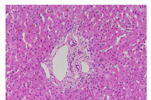

5例患者中有3例于我院进行了肝活组织病理学检查,患者编号分别为1、2和4。其中第1例患者肝穿刺活组织学检查为疾病的第1次发作,第2例患者为疾病的第2次发作,第4例患者为疾病的第9次发作。3例患者的病理学均提示肝脏小叶结构清晰,肝小叶内未见坏死灶;汇管区无明显扩大和明显炎症。仅仅表现为小叶中心毛细胆管淤胆(图1,图2,图3,图4)。其余2例患者就诊于我院时,已有多次典型的发作性黄疸,发作间期无任何症状,在治疗随访的过程中胆红素逐渐恢复正常,因此未行肝活组织病理学检查。

常见的导致直接胆红素升高的遗传性疾病包括:Dubin-Johnson综合征、Roter综合征、BRIC。Dubin-Johnson综合征的病理特点为:肝小叶中央静脉周围肝细胞内有大量脂褐素-黑色素复合物沉积;Roter综合征病理上无明显的改变,表现为正常的肝脏组织。BRIC病理学特征为:发作时小叶中心胆汁淤积,在扩张的毛细胆管、肝细胞、或Kupffer细胞内可见胆汁淤积。较少见的病变包括小叶中心局灶性单核细胞浸润伴或不伴有肝细胞变性、坏死;偶有细胆管增生。随着发作缓解,肝脏病理改变逐步恢复正常。我科5例患者中有3例于我院进行了肝活组织病理学检查,其中1例患者虽然经历了9次发作,但其肝组织仅仅表现为小叶中心毛细胆管淤胆,没有肝小叶及汇管区的慢性损伤表现。符合BRIC的病理表现。